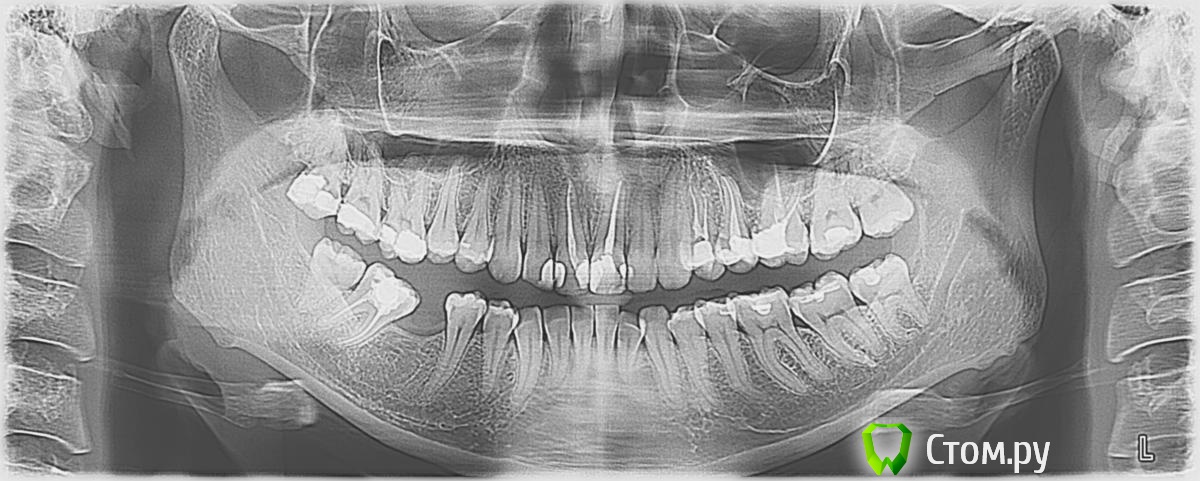

mois_kamchatka Опубликовано 8 декабря, 2013 Поделиться Опубликовано 8 декабря, 2013 Здравствуйте, помогите, пожалуйста, вылечить зубы. В августе этого года почувствовала сильную боль в области 25 и 26 зубов, обратилась к стоматологу, в итоге у обоих зубов удалили нервы,боль на некоторое время пропала. В ноябре область 24, 25, 26 зубов начала реагировать на горячее. Находилась на отдыхе в Украине, пришла в стоматологический кабинет - долго не могли определить какой зуб реагирует (лили из шприца горячую воду и т.д.). Так как на следующий день нужно было лететь, удалили нерв и в 24 зубе. По началу казалось, что болеть перестало. Однако через 2 дня реакция на горячее усилилась...Месяц промучилась (за границей обратилась за лечением, сказали, что т.к. 24,25,26 депульпированы, осталось удалить 27 и точно все пройдет, я отказалась), опять пошла ко врачу. Сделали снимки этих трех зубов, она говорит все ОК, наверное болит десна...Боль только на горячее, очень резкая (аж в пот бросает), постепенно проходит, если набрать в рот холодной воды проходит быстрее. В итоге врач отправила выяснять какой из зубов болит домой ("как поймешь - приходи"), а очень хочется горячего чая . Сегодня сходила сделала панорамный снимок, помогите определиться, что делать?? Спасибо. Ссылка на комментарий

IvanK Опубликовано 9 декабря, 2013 Поделиться Опубликовано 9 декабря, 2013 Здравствуйте. Нужно провести тест на витальность зубов ( жив или нет)Возможно , поблема в 28 24. 25. 26 нуждаются в протезировании. Ссылка на комментарий

Sir Edward'S Опубликовано 9 декабря, 2013 Поделиться Опубликовано 9 декабря, 2013 Здравствуйте .Проверьте на витальность ( жива пульпа или нет ) 27Провторное эндодонтическое лечение 26 зуба Ссылка на комментарий